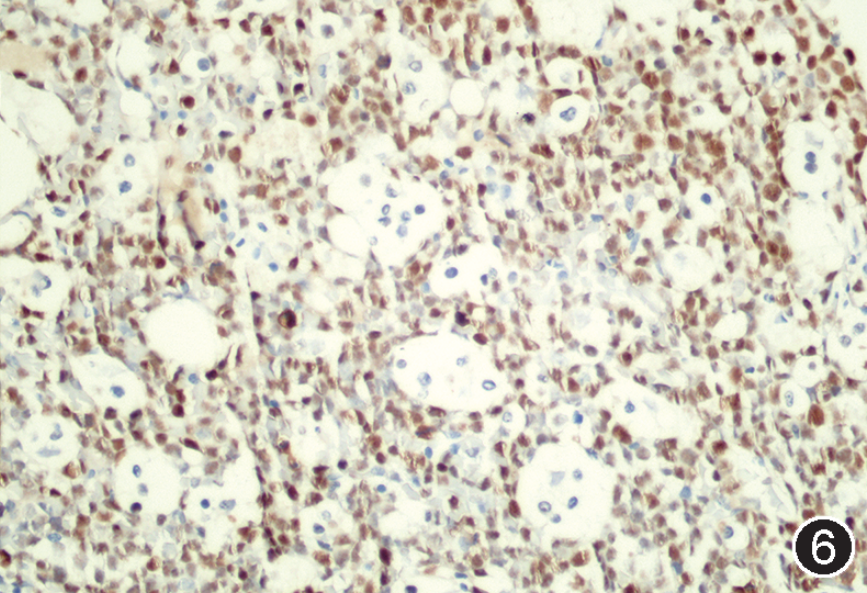

图注:图1 骨髓涂片中的肿瘤细胞(瑞氏染色,×1 000);图2 骨髓活检中的肿瘤细胞(HE, 高倍放大);图3 免疫组织化学染色,CD20部分阳性(EnVision法,中倍放大);图4 免疫组织化学染色,CD19阳性;图5 免疫组织化学染色,CD10阳性;图 6 免疫组织化学染色,MYC阳性,图 7 免疫组织化学染色,bcl-2阴性;图 8 免疫组织化学染色,Ki-67阳性指数约 80%。

根据以上检查结果,需要考虑的淋巴瘤类型包括BL、HGBL、原始细胞标记阴性B-ALL(占B-ALL<5%)以及罕见CD5-CD10+MCL的母细胞变型,须进一步进行免疫组化(包括CyclinD1、CD10、BCL6、MUM1、MYC、BCL2、Ki67)、染色体核型、FISH检测(MYC、BCL2、BCL6、IgH-CCND1)以及白血病融合基因检测加以区分。最终流式细胞学示肿瘤细胞CD38强表达、表达sIgM、sIgD和胞膜Kappa,免疫组化CyclinD1-,细胞遗传学示复杂核型,FISH检测MYC和bcl-6基因重排阳性,白血病52种融合基因阴性,二代测序提示存在TP53、CCND3、MYC、TCF3、FOXO1等HGBL、DLBCL中而非B-ALL/LBL中的常见基因突变类型,因此综合诊断为HGBL伴MYC和bcl-6基因重排。